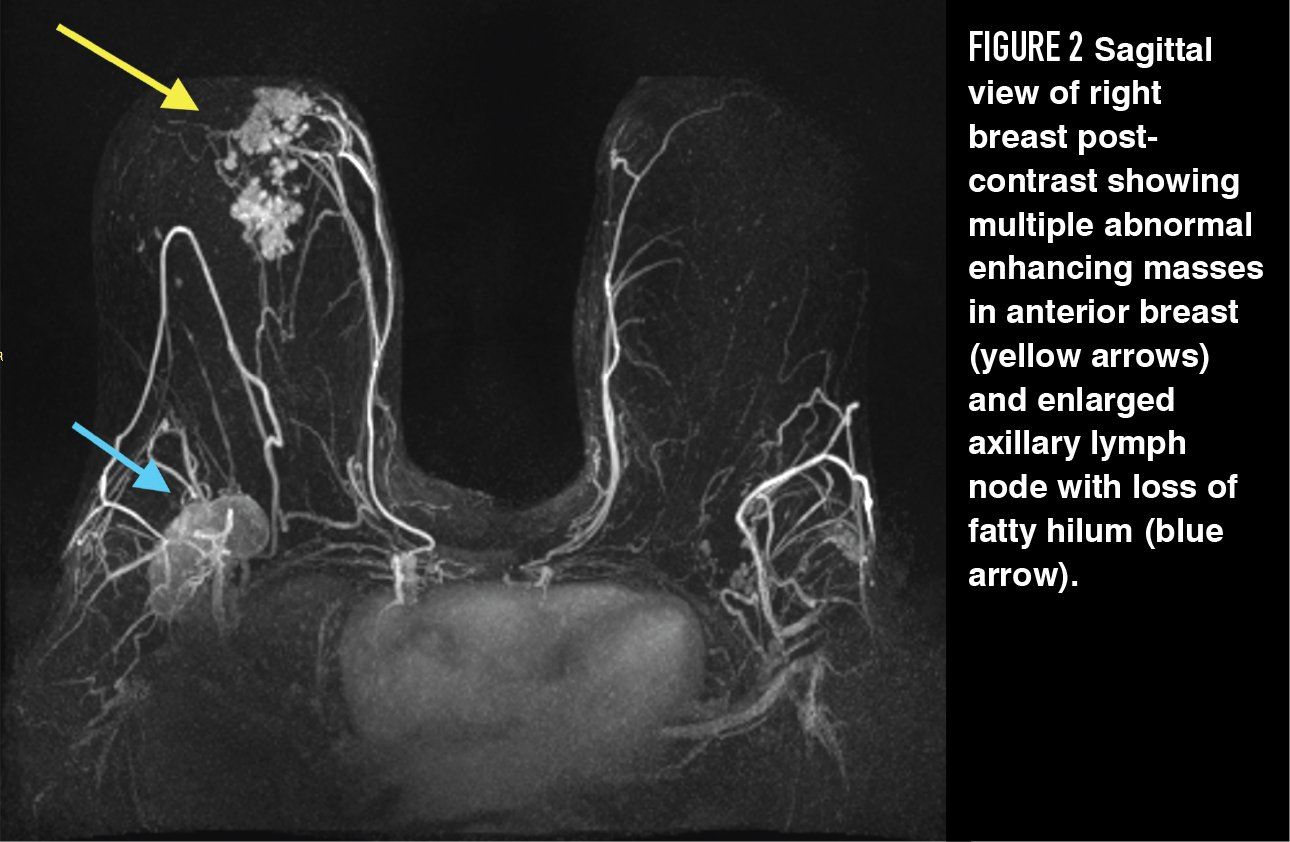

The incremental additional clinical information that is gained with use of GBCA in MRI evaluation of variant pelvic anatomy and suspected benign pathology is small. Adding GBCA has been shown to improve evaluation of myometrial invasion from endometrial carcinoma13 and identification of the correct primary tumor when there are multiple sites of biopsy-proven uterine adenocarcinoma.14 Contrast may also be useful in identifying vulvar cancers and occult inguinal metastases15 and it has shown to be useful in identifying neoplastic nodules within complex adnexal lesions and distinguishing endometriosis from pelvic inflammatory disease.16,17